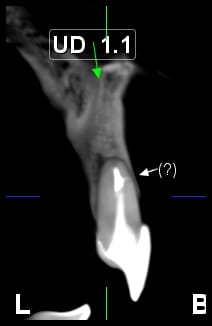

Fisura tratamiento conducto por corte transversal

Quisiera saber si una fisura en tratamiento de conducto, visto por corte transversal, ¿es causal de extracción?